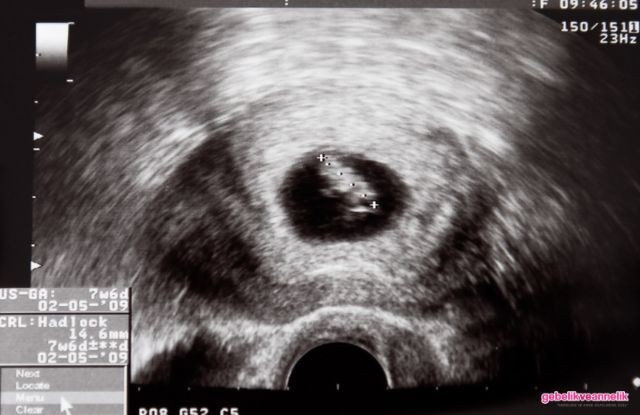

8. Hafta Anne Karnı Bebek Ultrason Görüntüleri